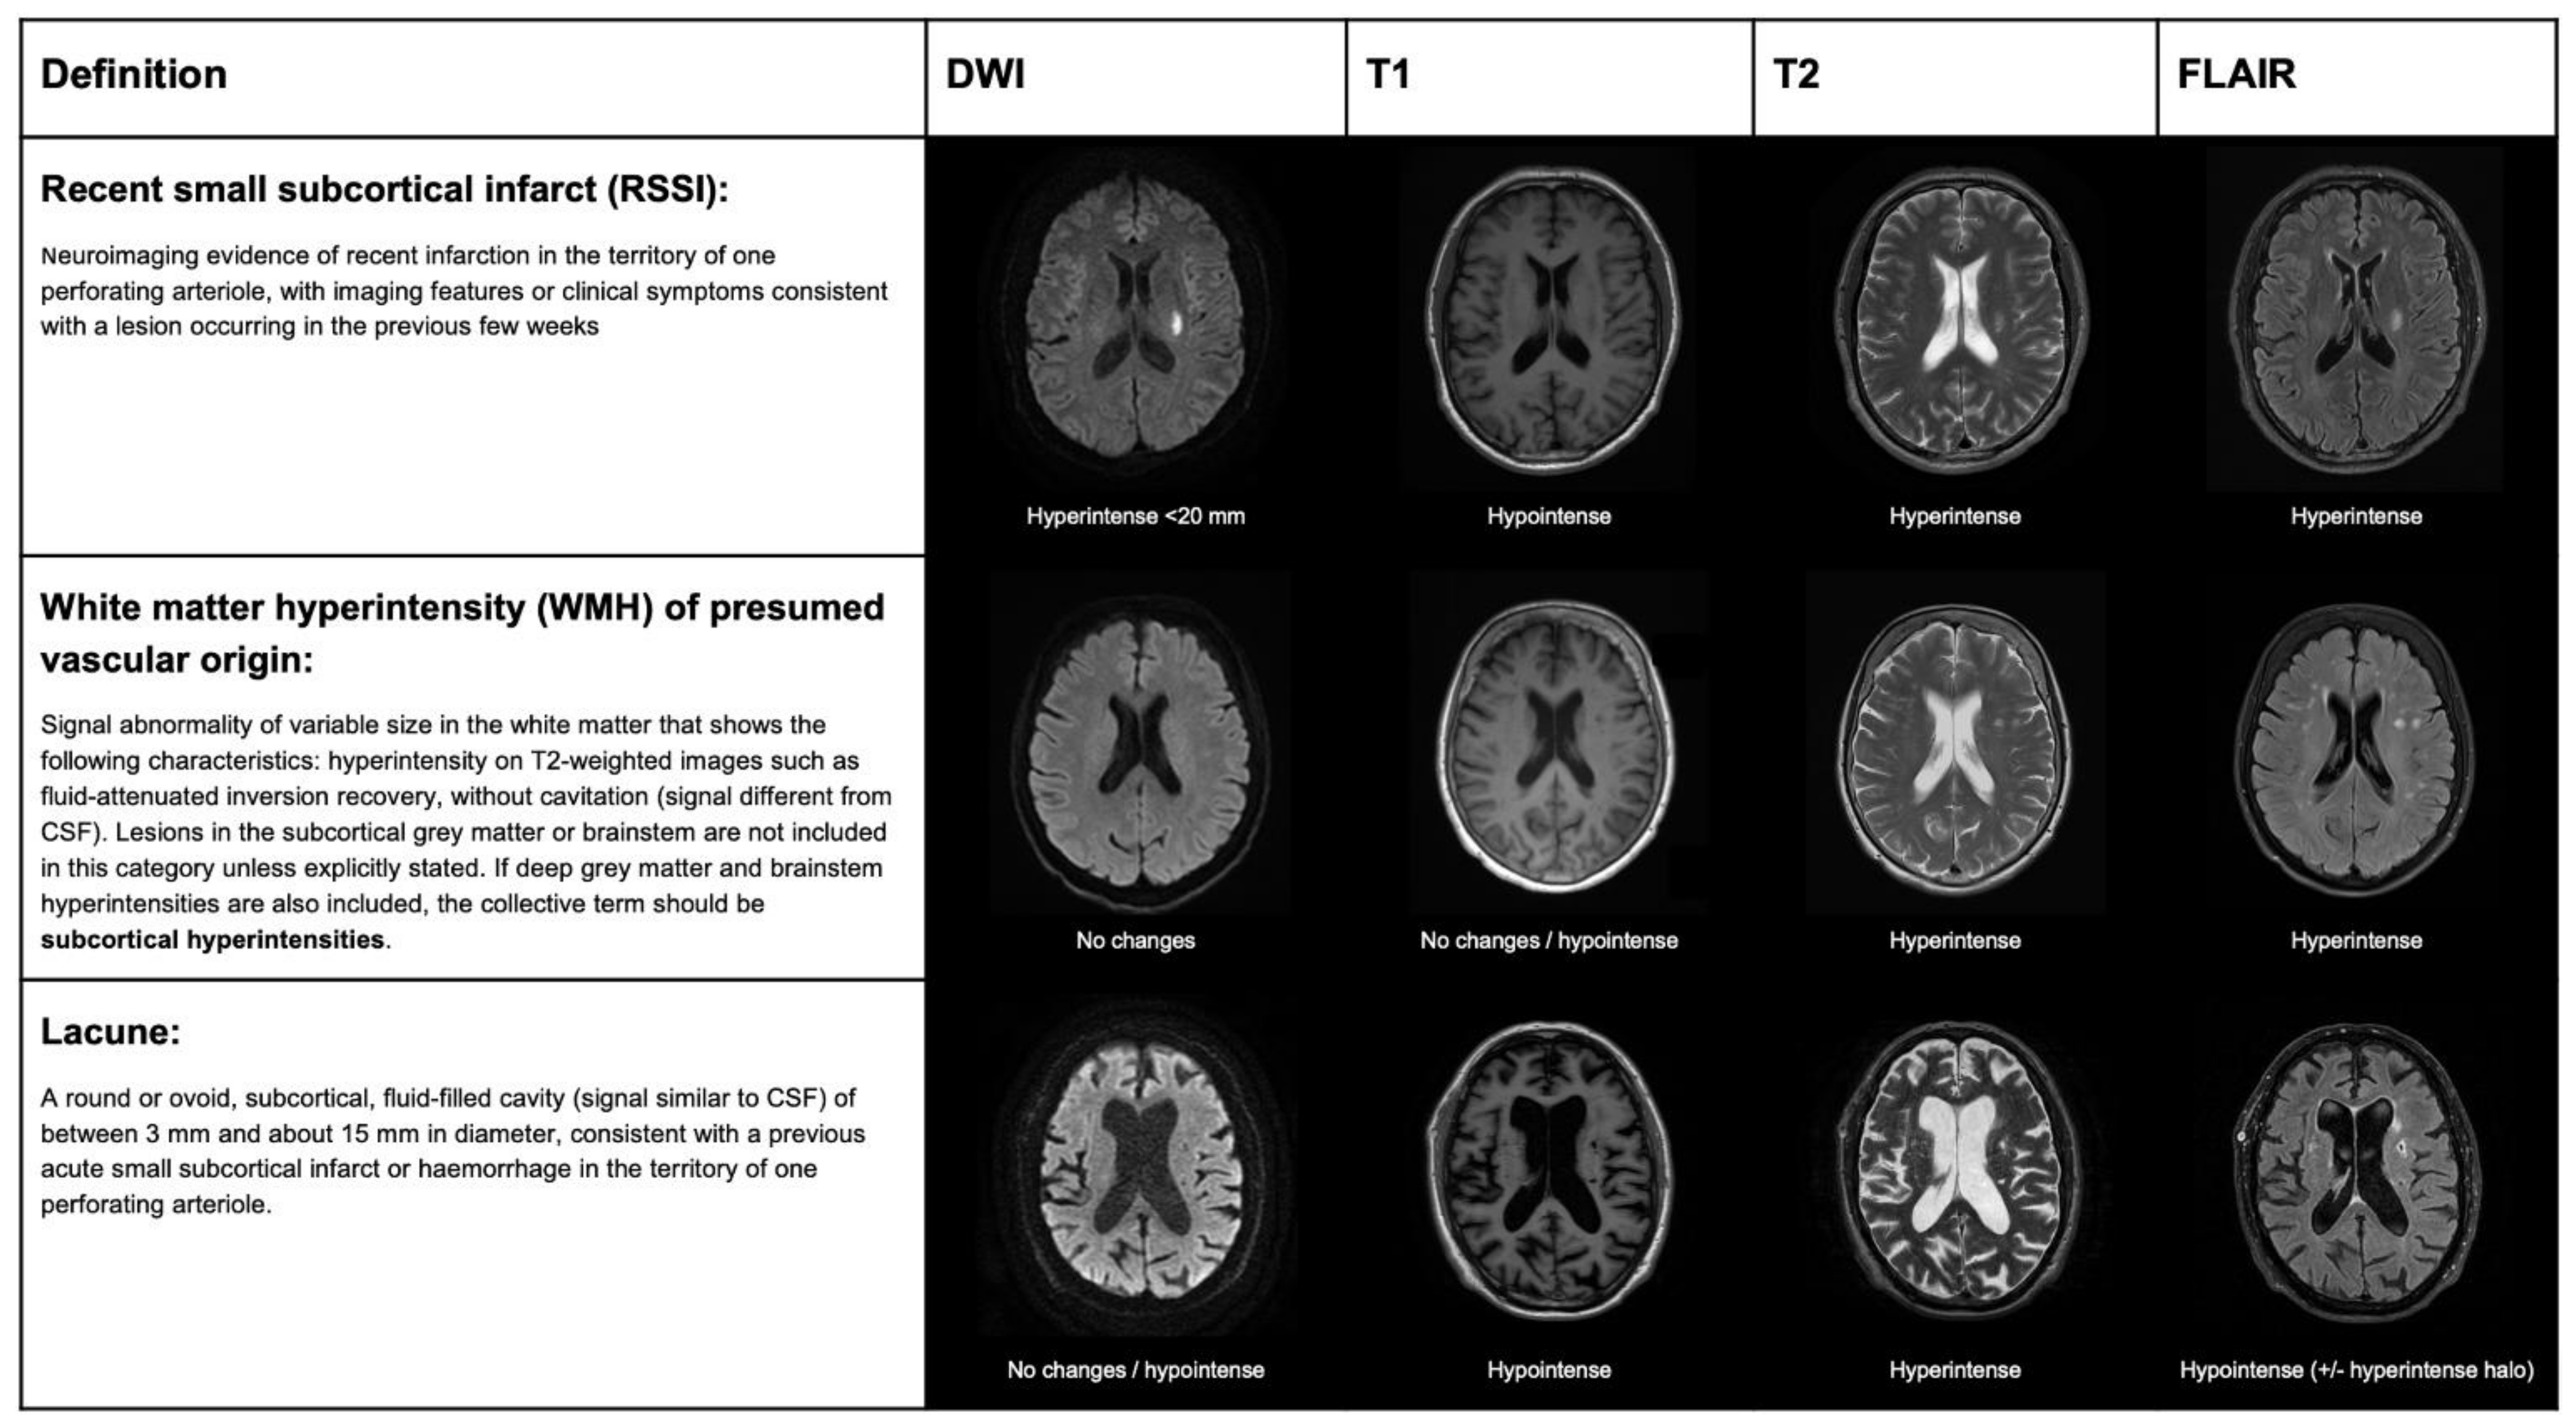

2. Terminology and Correlations between Histopathological, Clinical and Imaging Definitions